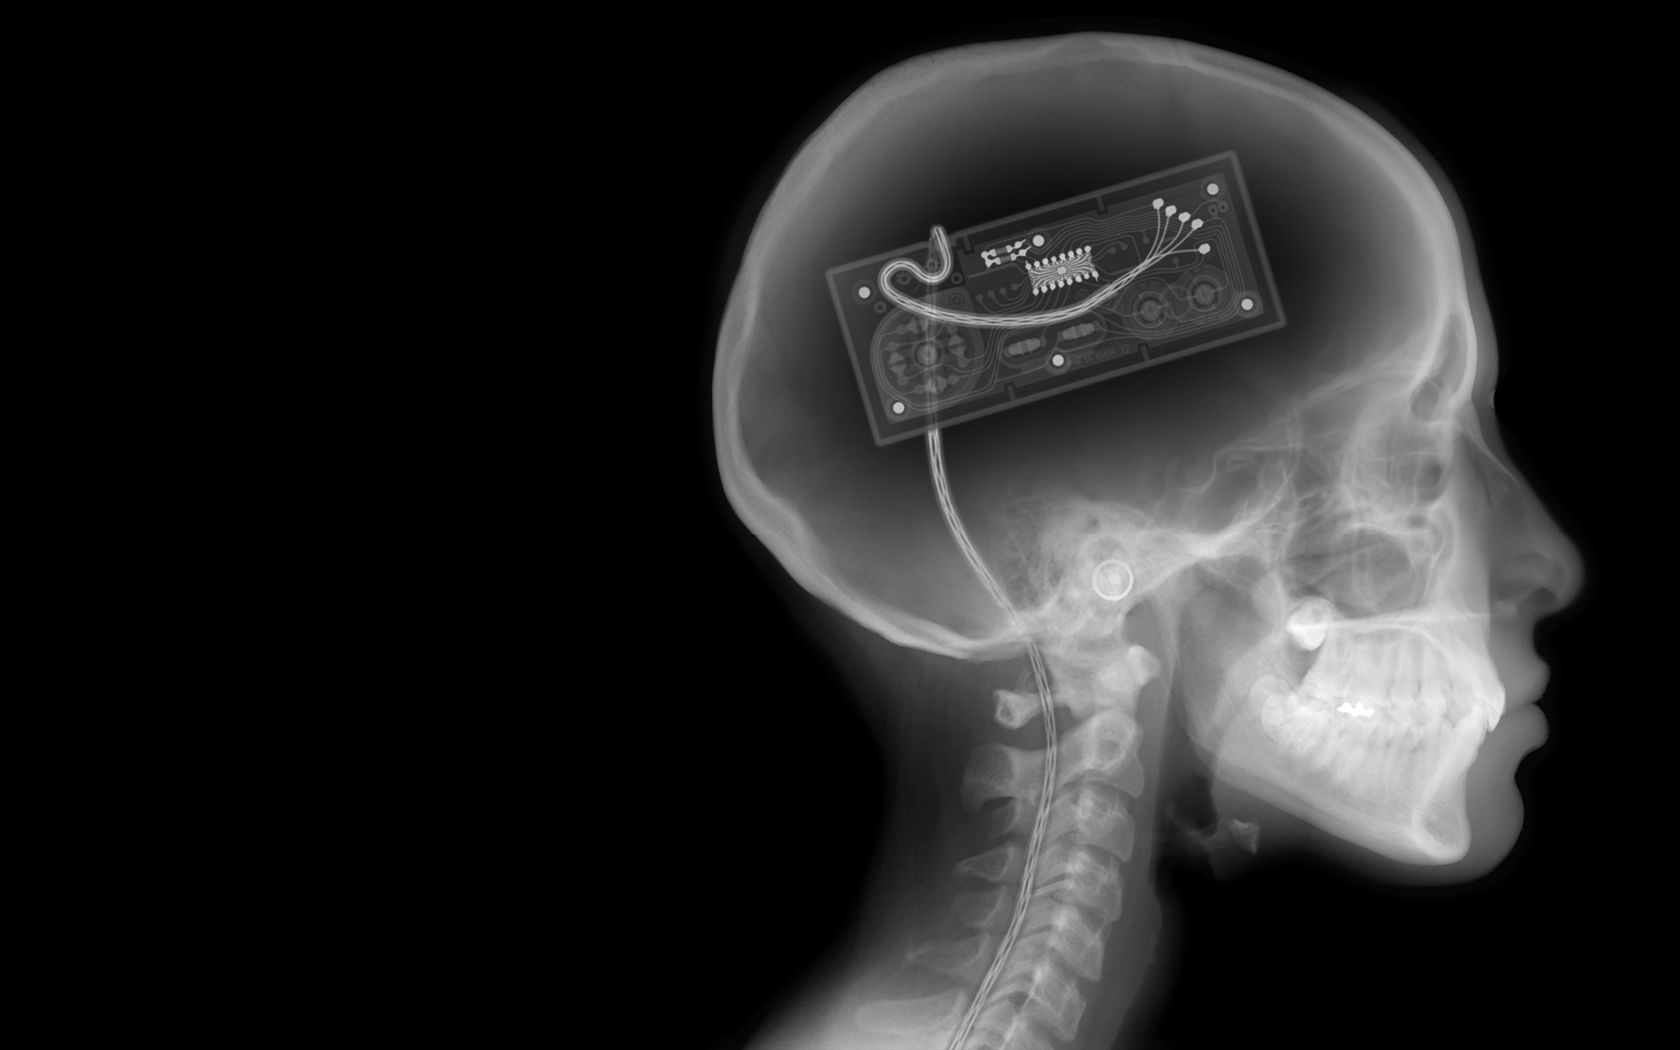

Анатомия мозга: Рентгеновские снимки для презентаций